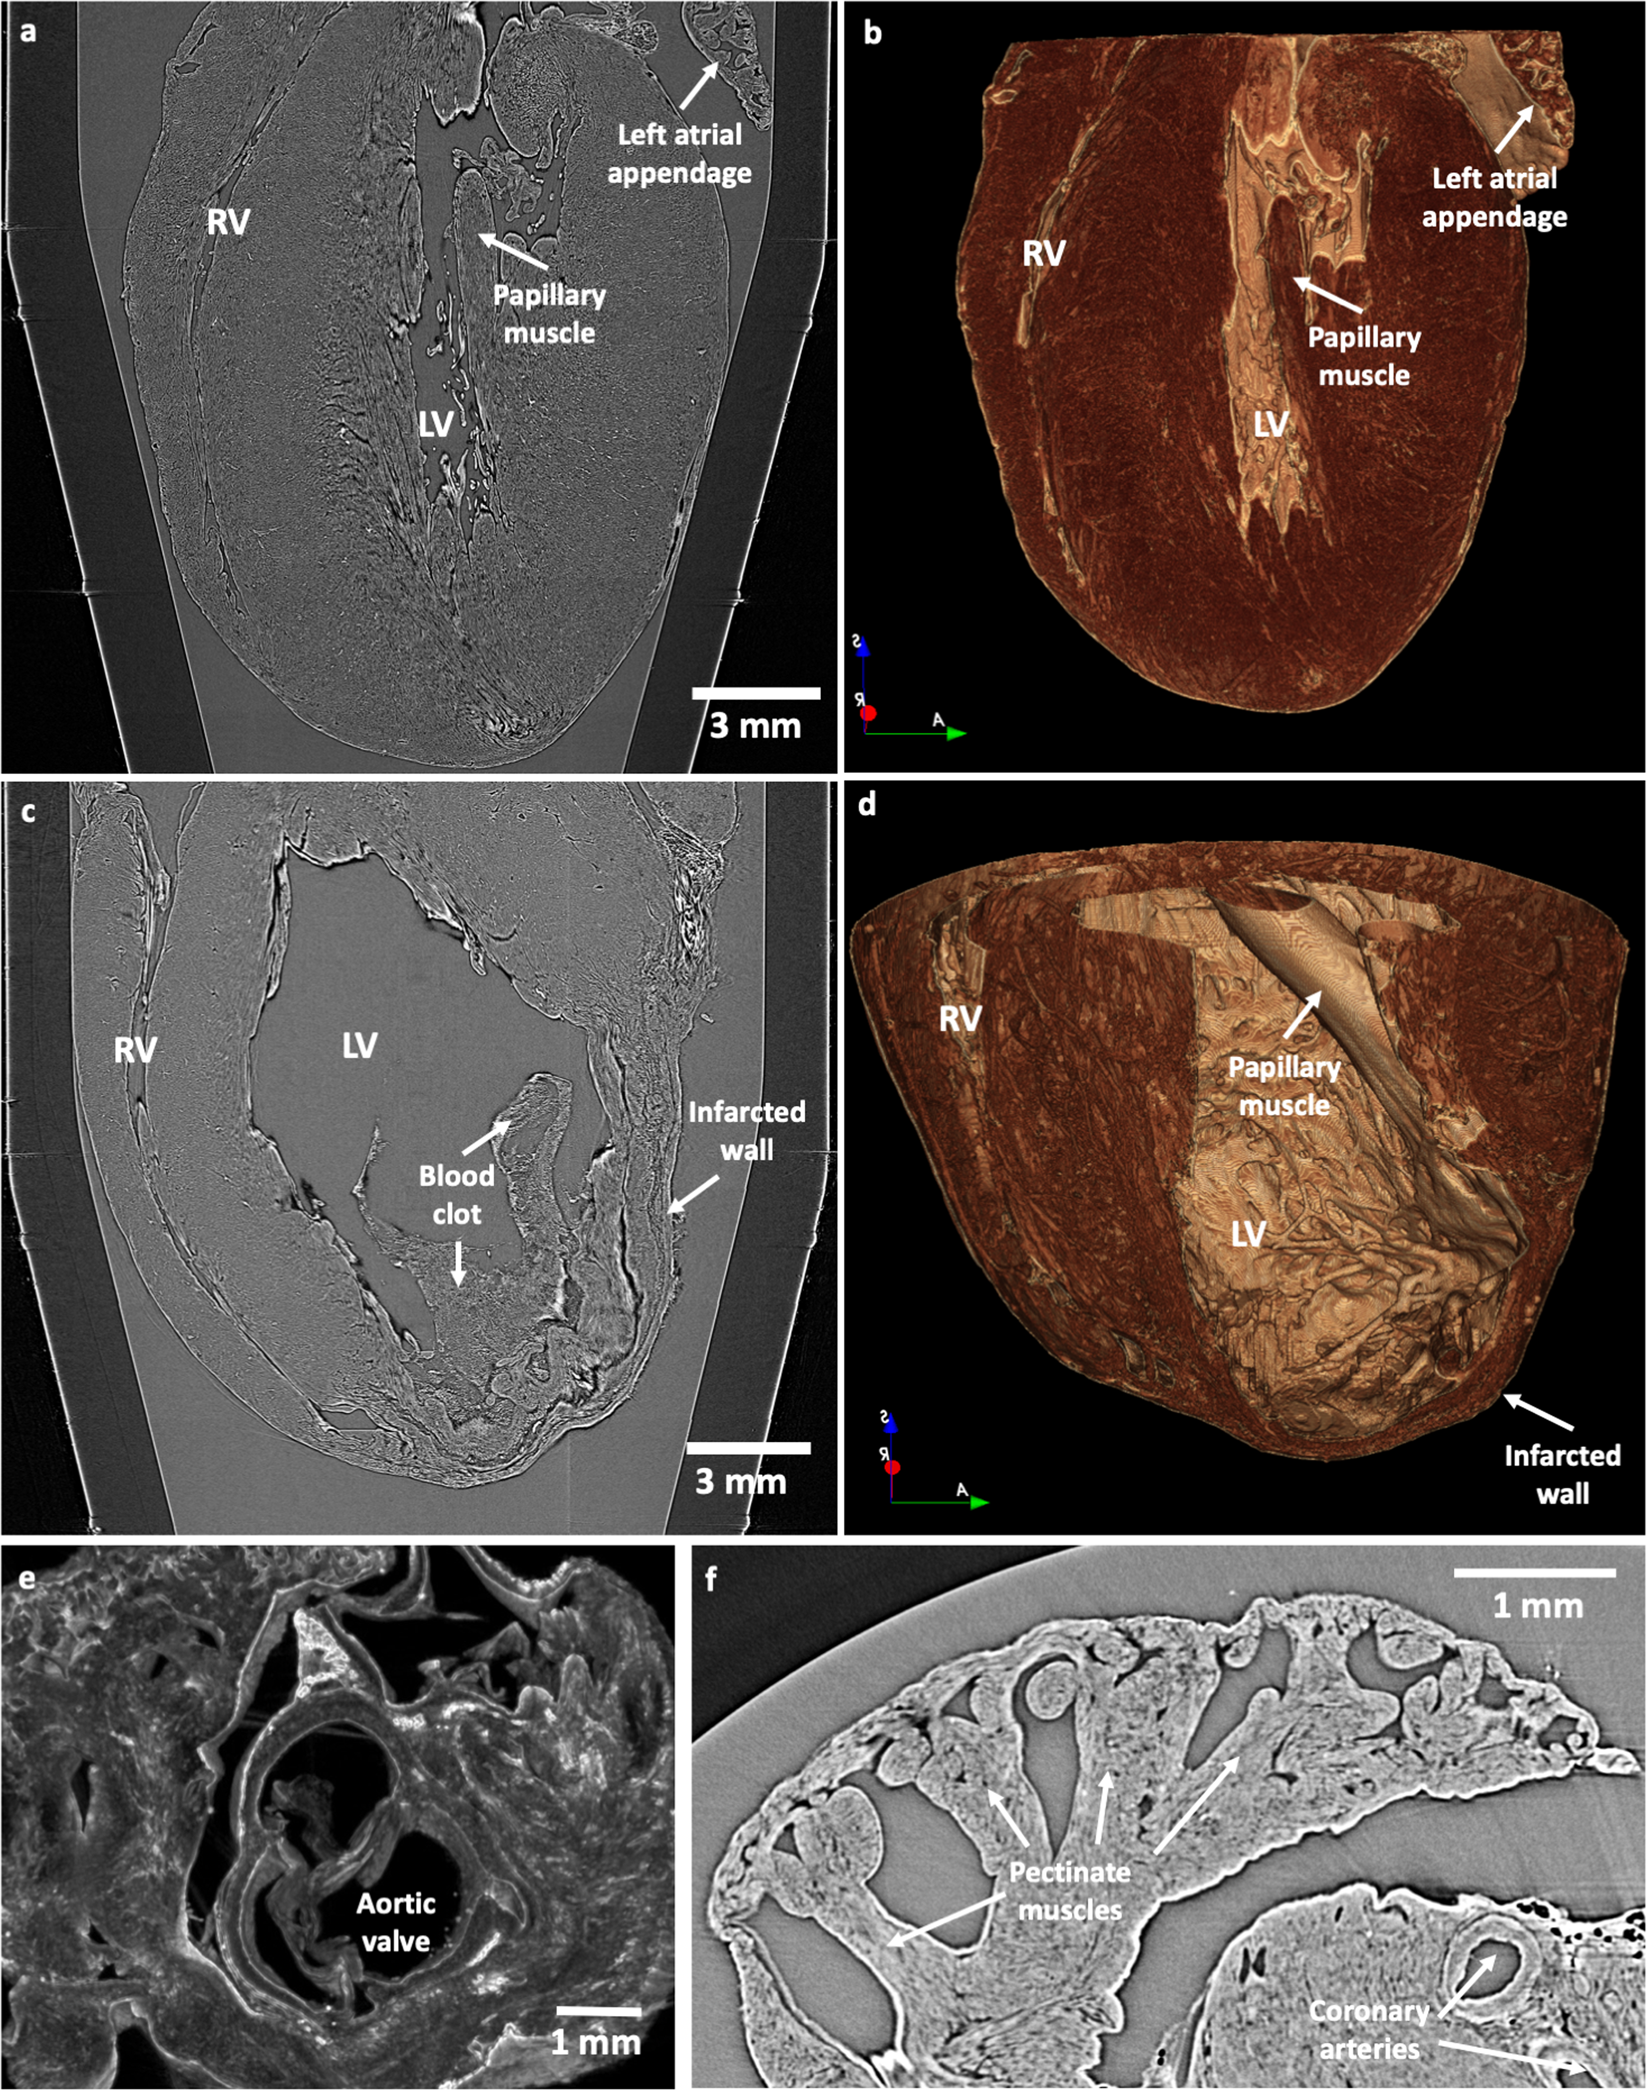

Figure 2

Whole heart geometry and detailed morphology assessment by PB-X-PCI. (a) Illustrative longitudinal PB-X-PCI virtual cut of the WKY heart at 5.8 μm pixel size (LR). (b) 3D volume rendered image showing the detailed internal structure of both ventricles extracted from the PB-X-PCI dataset in (a). (c) Illustrative longitudinal PB-X-PCI virtual cut of the LAD heart at 5.8 μm pixel size (LR). (d) 3D volume rendered image of the detailed internal structure of both ventricles and the infarcted region, extracted from the PB-X-PCI dataset in (c). (e) 3D detailed visualization of the aortic valve and surrounding structures in the SHR heart. (f) PB-X-PCI image (reconstructed with Paganin’s method) of the pectinate muscles in the left atrial appendage, as well as large coronary arteries in the myocardial wall of the SHR heart.